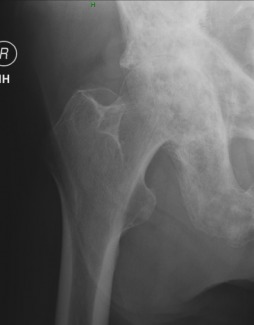

The right hip demonstrates joint space narrowing consistent with osteoarthritis. The key finding is the presence of sclerosis involving the visualized portion of the right innominate. The trabecular pattern also appears coarsened and Kohler's teardrop is opacified. The most common causes of opacification of Kohler's teardrop are blastic metastatic disease and Paget's disease. Also note the pelvic brim sign - thickening of the pelvic brim due to osteoblastic reaction, a helpful clue in distinguishing this condition from metastasis.

Diagnosis: Paget's disease

Common radiographic presentations include osteoporosis circumscripta and cotton wool of the skull, picture frame and ivory vertebra in the spine, the pelvic brim sign, opacified Kohler's teardrop, protrusio acetabuli in the pelvis, and a blade of grass/V shaped/candle flame lytic lesion in long bones.